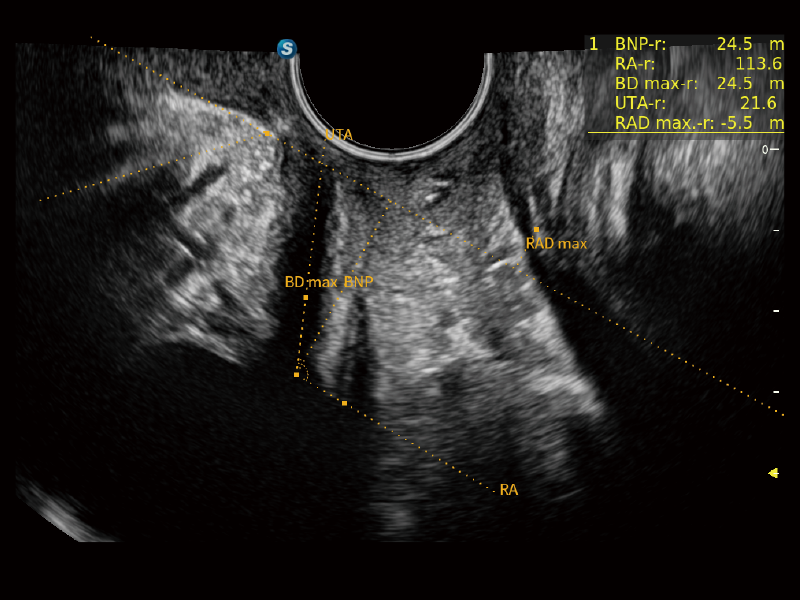

夢(mèng)溪?P80以“關(guān)愛女性”為基石,提供全方位的解決方案,量身定制以滿足女性的健康需求,涵蓋婦科、生殖健康檢查、產(chǎn)前篩查及產(chǎn)后康復(fù)等領(lǐng)域。